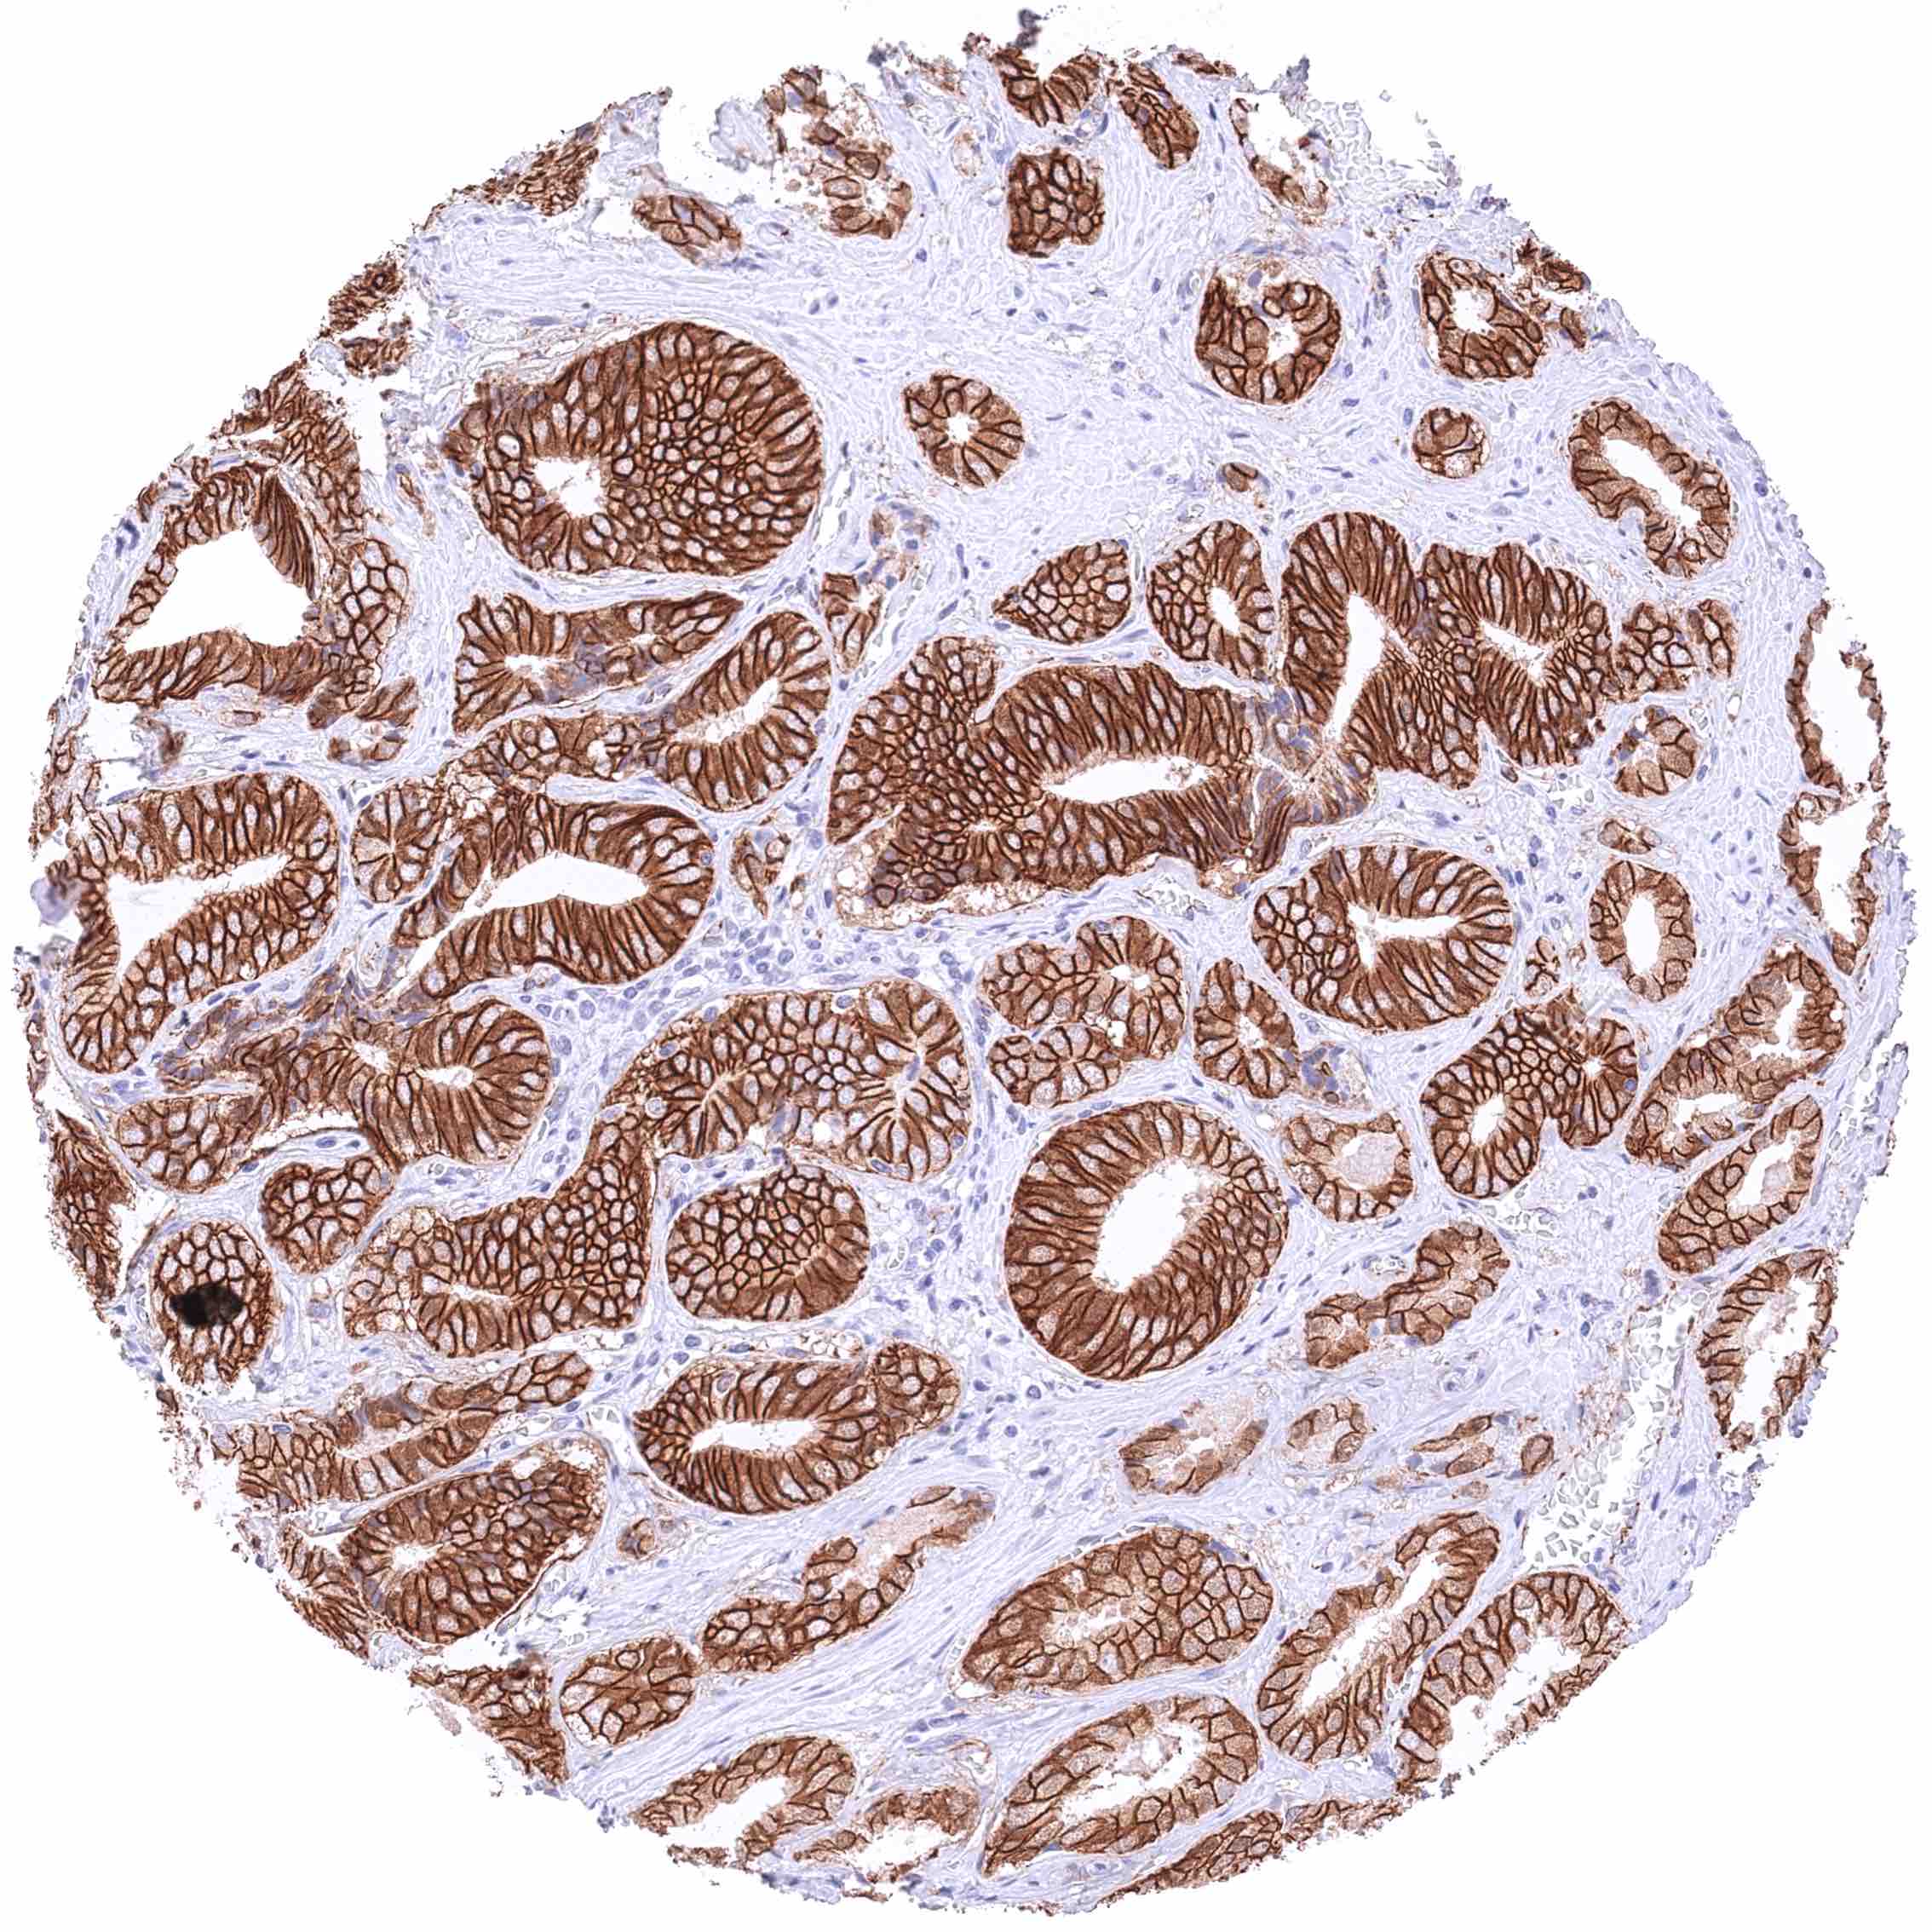

Prostate – Adenocarcinoma (Gleason 3+3=6) with strong membranous β-Catenin staining of tumor cells.

Prostate – Adenocarcinoma (Gleason 4+4=8) with strong membranous, moderate cytoplasmic, and strong nuclear β-Catenin staining of tumor cells.

Prostate – Adenocarcinoma (Gleason 5+5=10) with strong membranous, moderate cytoplasmic, and strong nuclear β-Catenin staining of tumor cells.